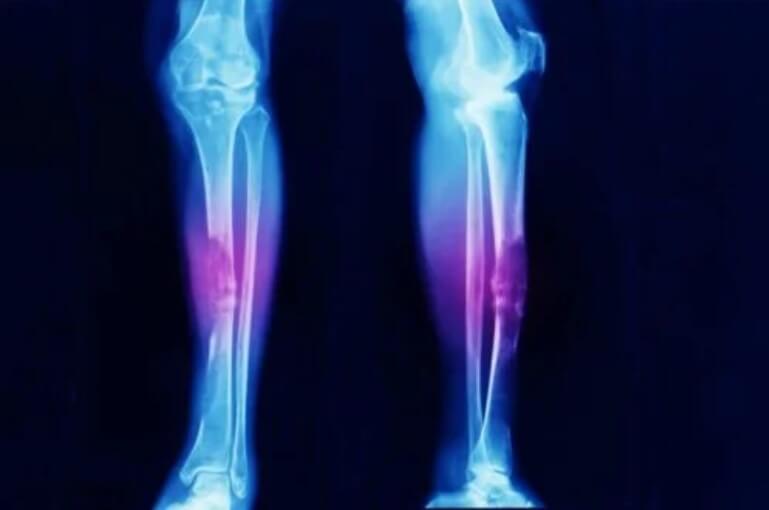

- Το οστεοσάρκωμα, όπως υποδηλώνει το όνομά του, είναι καρκίνος των οστών.

Τα σαρκώματα δεν είναι κοινά. Στην πραγματικότητα, διάφορες μελέτες δείχνουν ότι το οστεοσάρκωμα (ένας όγκος στον σκελετό) αντιπροσωπεύει μόνο το 0,2% όλων των κακοηθών καρκίνων. Αυτό σημαίνει ότι υπάρχει μια συχνότητα περίπου τριών περιπτώσεων ανά εκατομμύριο άτομα κάθε χρόνο.